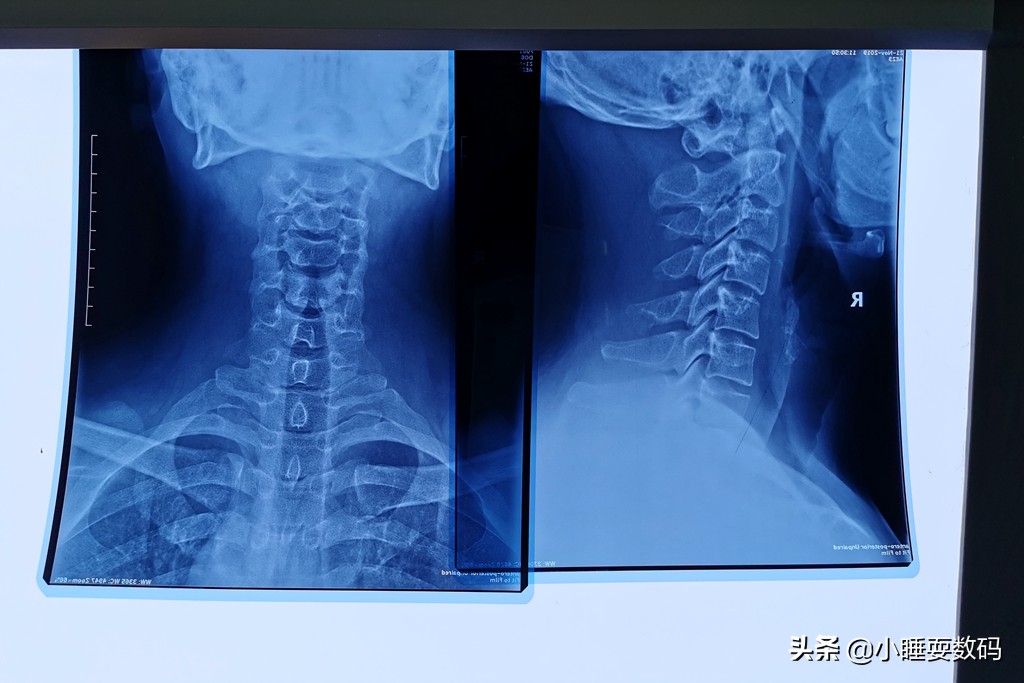

小睡本人也是一名颈椎病患者,工作上需要长期面对电脑,加上自己没有注意保养,久而久之也发展成了颈椎病。前几天甚至出现了头晕、乏力的症状,到医院拍了CT片子检查,颈椎的生理弧度几乎完全消失了,从上面的图片可以明显的看到。从医院开了药、买了牵引矫正器材,医生还叮嘱说睡觉不要枕太高的枕头睡觉,这是为什么呢?因为枕太高的枕头,脖子的姿势就相当于白天低头看手机。